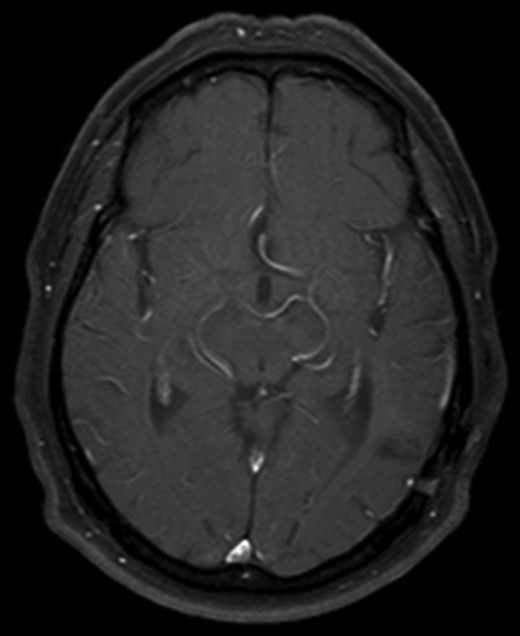

He made an uneventful recovery but presented 1 year later with intermittent dysphasia and confusion. MRI of the brain revealed a homogeneously enhancing lesion in the left posterior temporal lobe (Fig. 1). Staging CT scans identified no other lesions and this was felt to be an isolated metastasis. The patient had a craniotomy and excision of the tumour. Histopathology confirmed a high-grade neuroendocrine carcinoma with an identical immunohistochemical profile consistent with metastatic Merkel cell carcinoma (Fig. 2).

Axial T1 with Gadolinium MRI showing no evidence of recurrence at 10-year follow-up.